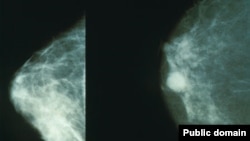

Эмчек рагынын алдын алыш үчүн ультраүндүк кароо болуп, дарыгерлер аялдарга кеңеш берүүдө.

Кыргызстанда көкүрөк рагына чалдыккан аялдардын 39 пайызы оорусу өтүшүп кеткенде адиске кайрылууда. Жылына 600дөн ашуун аял ушул ооруга кабылып жатат. (BCh)